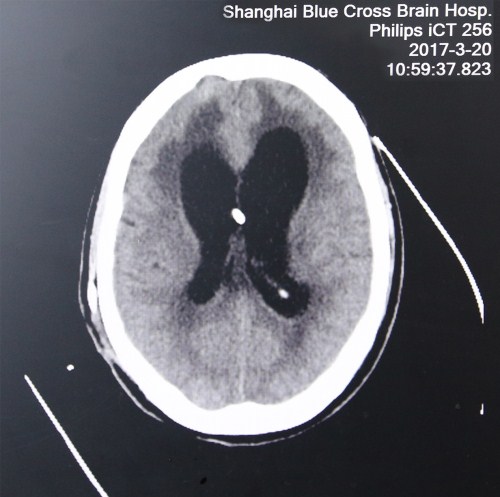

入院初头颅CT影像:之前做过分流手术,置入两分流管,脑室扩大、肿胀、有软化、渗出,脑压高

最近头颅CT影像:脑沟回明显,脑室缩小,脑压降低,重新置管分流后有效